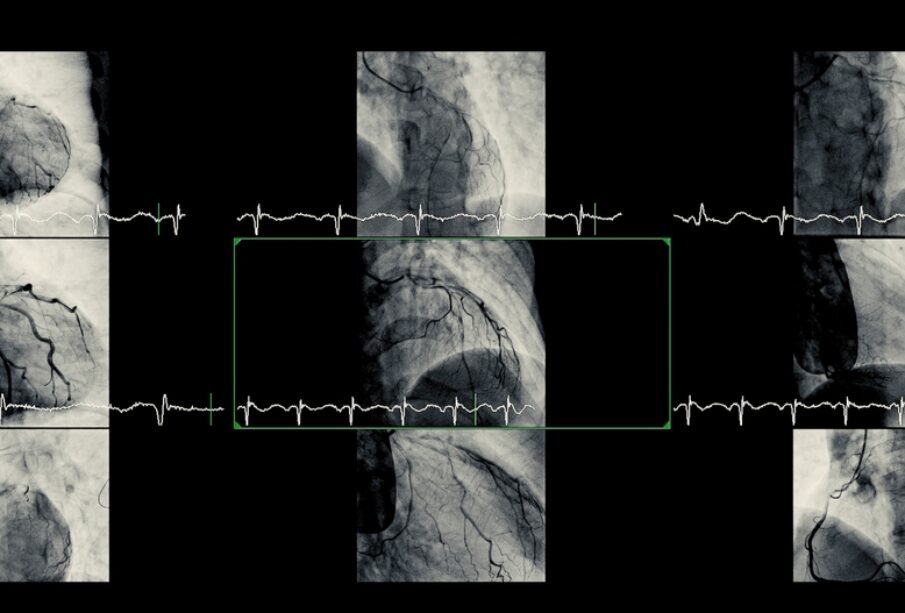

Angiogrāfija ir invazīvs izmeklējums, kurā pa asinsvadiem ievada katetru, caur to ievada kontrastvielu un vienlaikus veic rentgena vai ultrasonogrāfiskus attēlus. Šī metode ļauj tieši novērtēt artēriju anatomiju, nosprostojuma apmēru un asins plūsmu sirds asinsvados.